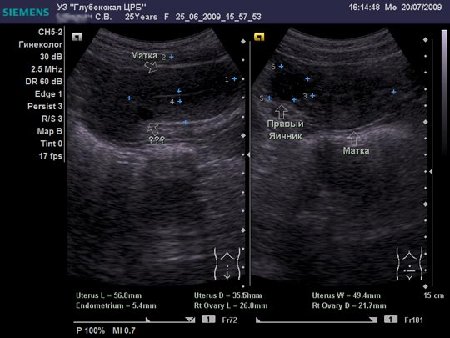

Женщина 25 лет предъявляет жалобы на периодически возникающую болезненность в нижних отделах живота, боли появились около 6-8 мес. Менструальная функция не нарушена. В анамнезе кесарево сечение, ребёнку 2,5 года.

- Сонограмма при первом обращении

Doc, на взгляд неспециалиста в гинекологическом УЗИ -

Nabothian cyst

Я тоже думал про наботовы желёзки, но меня смутил тот момент, что не явилось ли это образование следствием оперированной матки, лигатуры... ну чего-то там с ними... или что-то в этом духе????

Согласен, Наботова или эндо-цервикальная киста шейки. Ничего специфического.

Naboti пишем, эндометриоз в уме